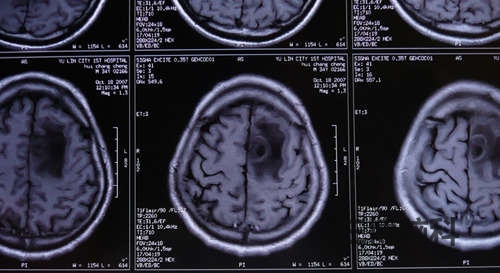

小脑蚓部占位性病变(囊肿)切除术案例

患者赵某某,40岁,男性,北京人,于2014年2月13日以阵发性头晕头痛3月,加重伴呕吐1周入院。 现病史: 患者于3月前2017-06-01

脑囊肿头痛病案

患者某某,男34岁,今年5月份开始头痛,一直很频繁,主要是右侧后部,剧烈疼痛,胀痛,已经严重影响工作和其他2017-06-01